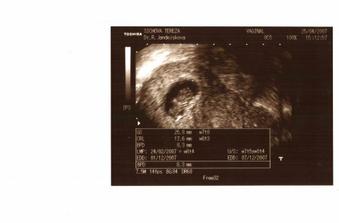

Tak takhle rosteme....1.12.2007 bychom už měli být ve třech: Tatínek Jirka, Maminka Tereza a já...Linda nebo Samuel...